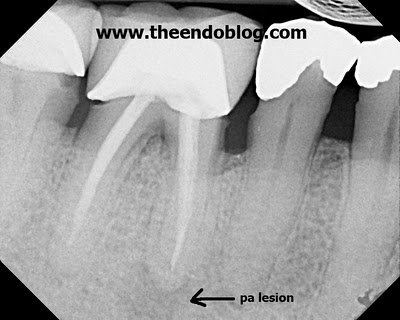

This pt presented in 2006 with an prior rct & acute apical abscess. Retx was recommended. A periapical lesion is noted on the distal root.